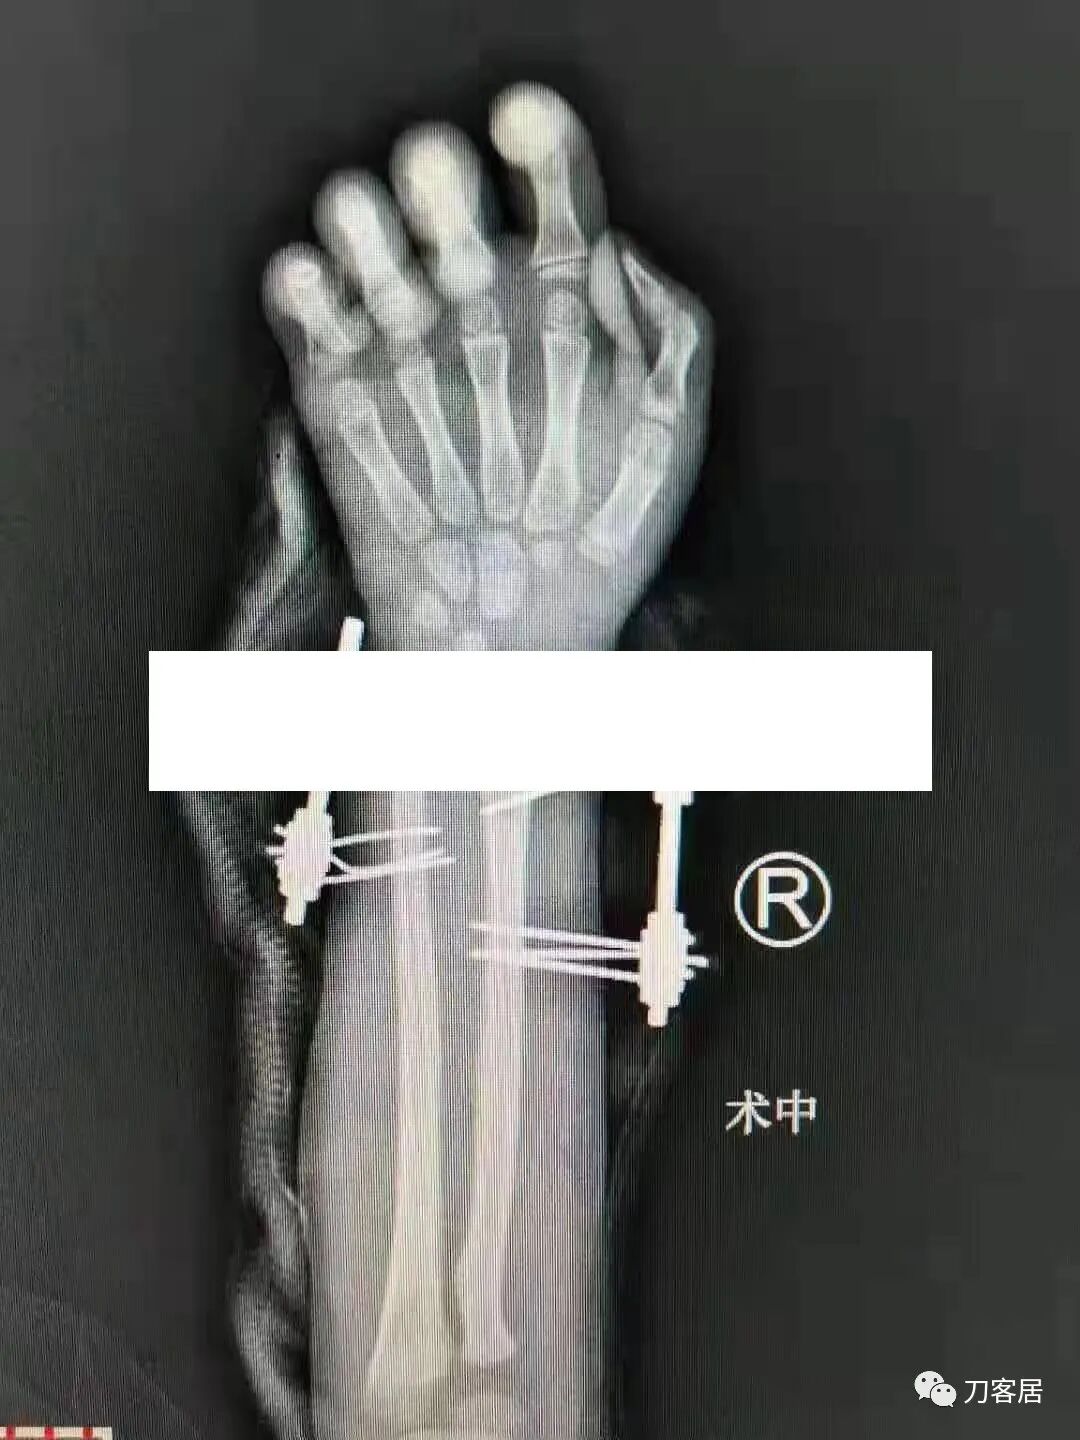

下面是这个6岁孩子,尺桡骨远端双骨折的术前及术后片子和外观照片。

2.  这个骨折处理起来也很简单,单纯的打石膏托或者中医的小夹板,或者正规的包括腕关节和肘关节的管型石膏外固定4周即可治愈该骨折。实在不行,如果这个孩子比较听话,不太调皮的话,用一本书,一个三角巾悬吊固定4周,都可以治愈该骨折。但是给这个患者用外固定架做了手术,而且桡骨远端的几颗克氏针距离骨折线太近,其中一枚克氏针进入到骨折间隙内。从这个术中图片来看,术者的外固定手术技术也有待于进一步的提高。毕竟术者应该还很年轻。从X线片来看,前臂及手的尺侧有不透光影,应该还使用了外固定石膏绷带托,而且我猜测应该是高分子的石膏绷带托,这个是纯属猜测,不一定是对的,不过如何解释前臂尺侧的不透光影呢?如果真是用了石膏绷带外固定的话,那为啥要做手术呢?外固定架术后就不该再用石膏绷带托辅助了。